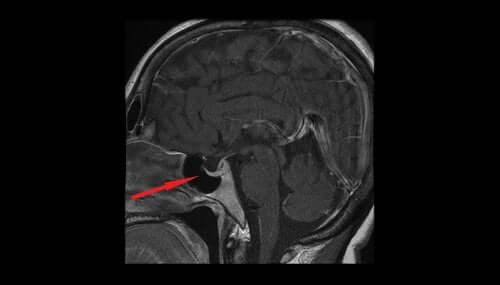

Ischemia del nervo ottico posttramautica Diagnosi e trattamento con staminali e trapianto liquido.

Decorso del nervo ottico e rapporto con altre strutture anatomiche Principali malattie del nervo ottico Il nervo ottico rappresenta l'inizio delle vie ottiche, ossia quell'insieme di strutture che, partendo dalla retina, collegano il bulbo oculare al cervello Questa componente è indispensabile per attivare in modo corretto la visione. Decorso del nervo ottico e rapporto con altre strutture anatomiche Principali malattie del nervo ottico Il nervo ottico rappresenta l'inizio delle vie ottiche, ossia quell'insieme di strutture che, partendo dalla retina, collegano il bulbo oculare al cervello Questa componente è indispensabile per attivare in modo corretto la visione. Poiché i pazienti possono danneggiare un solo nervo olfattivo alla volta, che non possono essere immediatamente a conoscenza del danno, attribuendo una diminuzione del senso dell'olfatto per il naso chiuso o non se ne accorga la sensibilità ridotta agli odori.

Nervo Ottico Danneggiato cause e sintomi Blog di News Nervo ottico, notizie ;. Non ti preoccupare troppo in quanto può essere trattata con semplici rimedi naturali Questi sono i sensi che diamo per scontato e quando li perdiamo, ci rendiamo conto di quanto siano importanti. Articoli, video ed opinioni su Nervo ottico nell'ambito medico sanitari Il nervo ottico lascia l'orbita ed entra nella cavità cranica attraverso il forame ottico dello sfenoide, da qui, in corrispondenza del solco dello sfenoide, le fibre del nervo ottico si.

Il nervo ottico è uno dei dodici nervi cranici Si può definire una proiezione esterna del sistema nervoso centrale grazie a cui gli impulsi luminosi percepiti dalla retina vengono veicolati verso la corteccia occipitale dove vengono convertiti in sensazione visiva E’ composto da oltre un milione di fibre che si raccolgono in fasci separati da. I nervi infiammati sono, spesso, una patologia di facile risoluzione In altri casi, invece, possono essere un campanello d’allarme per problemi più seri, carenze vitaminiche, soprattutto di B12 o patologie di base correlate I nervi infiammati si definiscono, in medicina, “neuropatia”, in quanto possono dipendere sia da una causa neurologica che da una causa nervosa Indice1. Controlla anche la dimensione delle pupille in risposta alla luce.

Qual è la sua funzione?. Qui, il nervo ottico proveniente da ciascun occhio si divide e metà delle fibre nervose provenienti da ogni lato passa dall’altro lato Da questa organizzazione, il lato destro del cervello riceve le informazioni dal campo visivo sinistro di entrambi gli occhi e il lato sinistro riceve le informazioni dal campo visivo destro di entrambi gli occhi. Olfattiva danni ai nervi e riparazione Il tuo nervo olfattivo è responsabile per l'olfatto e la vostra capacità di rilevare i sapori di cibi e bevande che si consumano Danni al nervo olfattivo può essere debilitante e la condizione colpisce molte persone in tutto il mondo Quante persone.